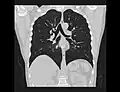

Blood supply

3D rendering of a high-resolution CT scan of the thorax. The anterior thoracic wall, the airways and the pulmonary vessels anterior to the root of the lung have been digitally removed in order to visualise the different levels of the pulmonary circulation.

The lungs have a dual blood supply provided by a bronchial and a pulmonary circulation.[4] The bronchial circulation supplies oxygenated blood to the airways of the lungs, through the bronchial arteries that leave the aorta. There are usually three arteries, two to the left lung and one to the right, and they branch alongside the bronchi and bronchioles.[32] The pulmonary circulation carries deoxygenated blood from the heart to the lungs and returns the oxygenated blood to the heart to supply the rest of the body.[32]